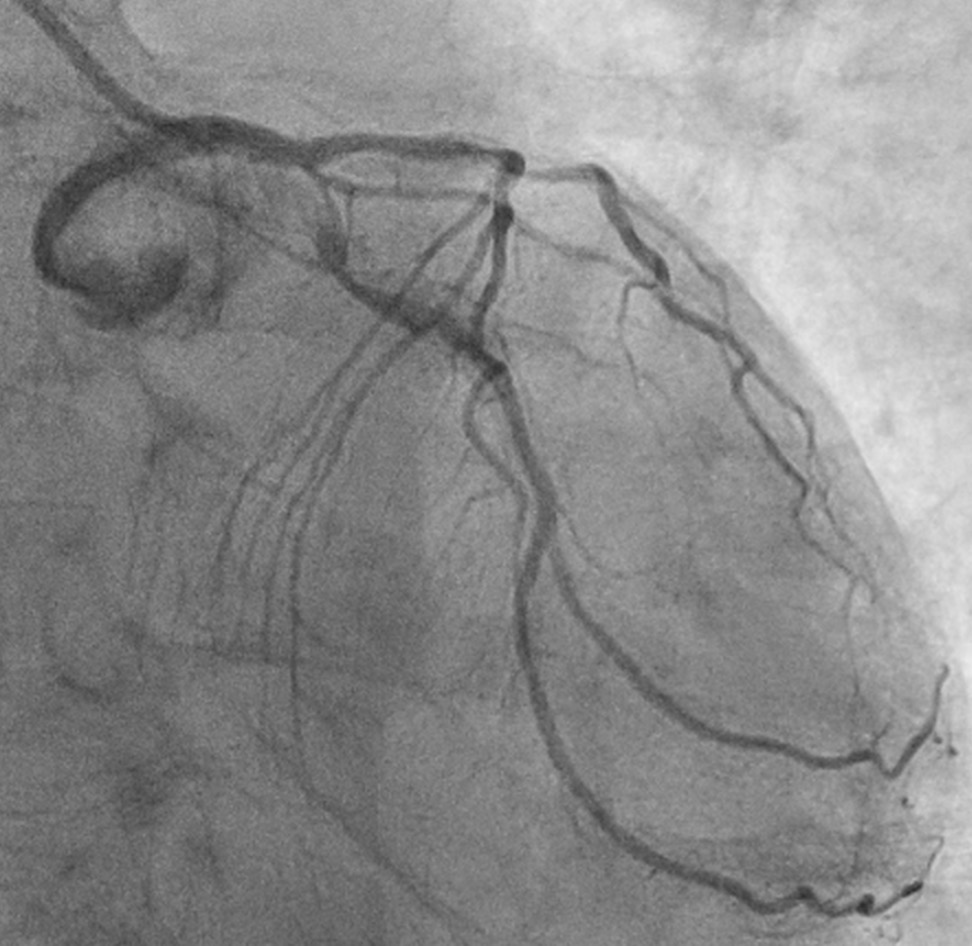

This confirmed severe calcific triple vessel disease. Severe mid LAD diagonal bifurcation stenosis (Medina 1,1,1). Severe LCx ostial and mid stenoses with large ostial calcific nodule. Severe ostial RCA stenosis and distal RCA CTO receiving collateral supply from the septal perforators. CABG was declined due to high surgical risk. After extensive discussions with the patient, his family, and the Vascular Surgical team, high risk vascular and coronary interventions were undertaken.

The Vascular team performed aortoiliac revascularisation to concurrently treat his peripheral vascular disease and allow for femoral access for CHIP. Kissing covered stents were placed from the abdominal aorta to bilateral CIAs and EIAs using the ¡°pave and crack¡± technique with chimney stenting to the IMA. After recovery, single access for Impella CP supported high-risk PCI (SHiP) was performed via the left femoral artery with a 7F sheath through the 14F Impella sheath. Intervention began with the LAD using rotational atherectomy (1.25mm burr) but led to hemodynamic instability despite Impella support, requiring emergency intubation and dopamine infusion. Significant blood loss was noted from the SHiP access due to the inadvertent migration of the PCI sheath proximally, and addressed by repositioning the sheath and transfusion. Once stabilised, the LAD, diagonal, and LCx arteries were treated with rotational atherectomy (1.25mm burr). The LCx had follow up orbital atherectomy, and scoring balloon angioplasty for a large ostial calcific nodule. The left main stem bifurcation was treated with drug eluting stents using OCT guided nano crush technique (3.5/28mm LMS-LAD, 3.5/28mm LCx). The first diagonal and mid LCx were treated with drug eluting balloons (2.5/30mm, 2.5/20mm). Final POT was performed in the LMS (4.0/8mm non-compliant at 18atm). Final OCT and angiography showed satisfactory result with TIMI 3 flow.